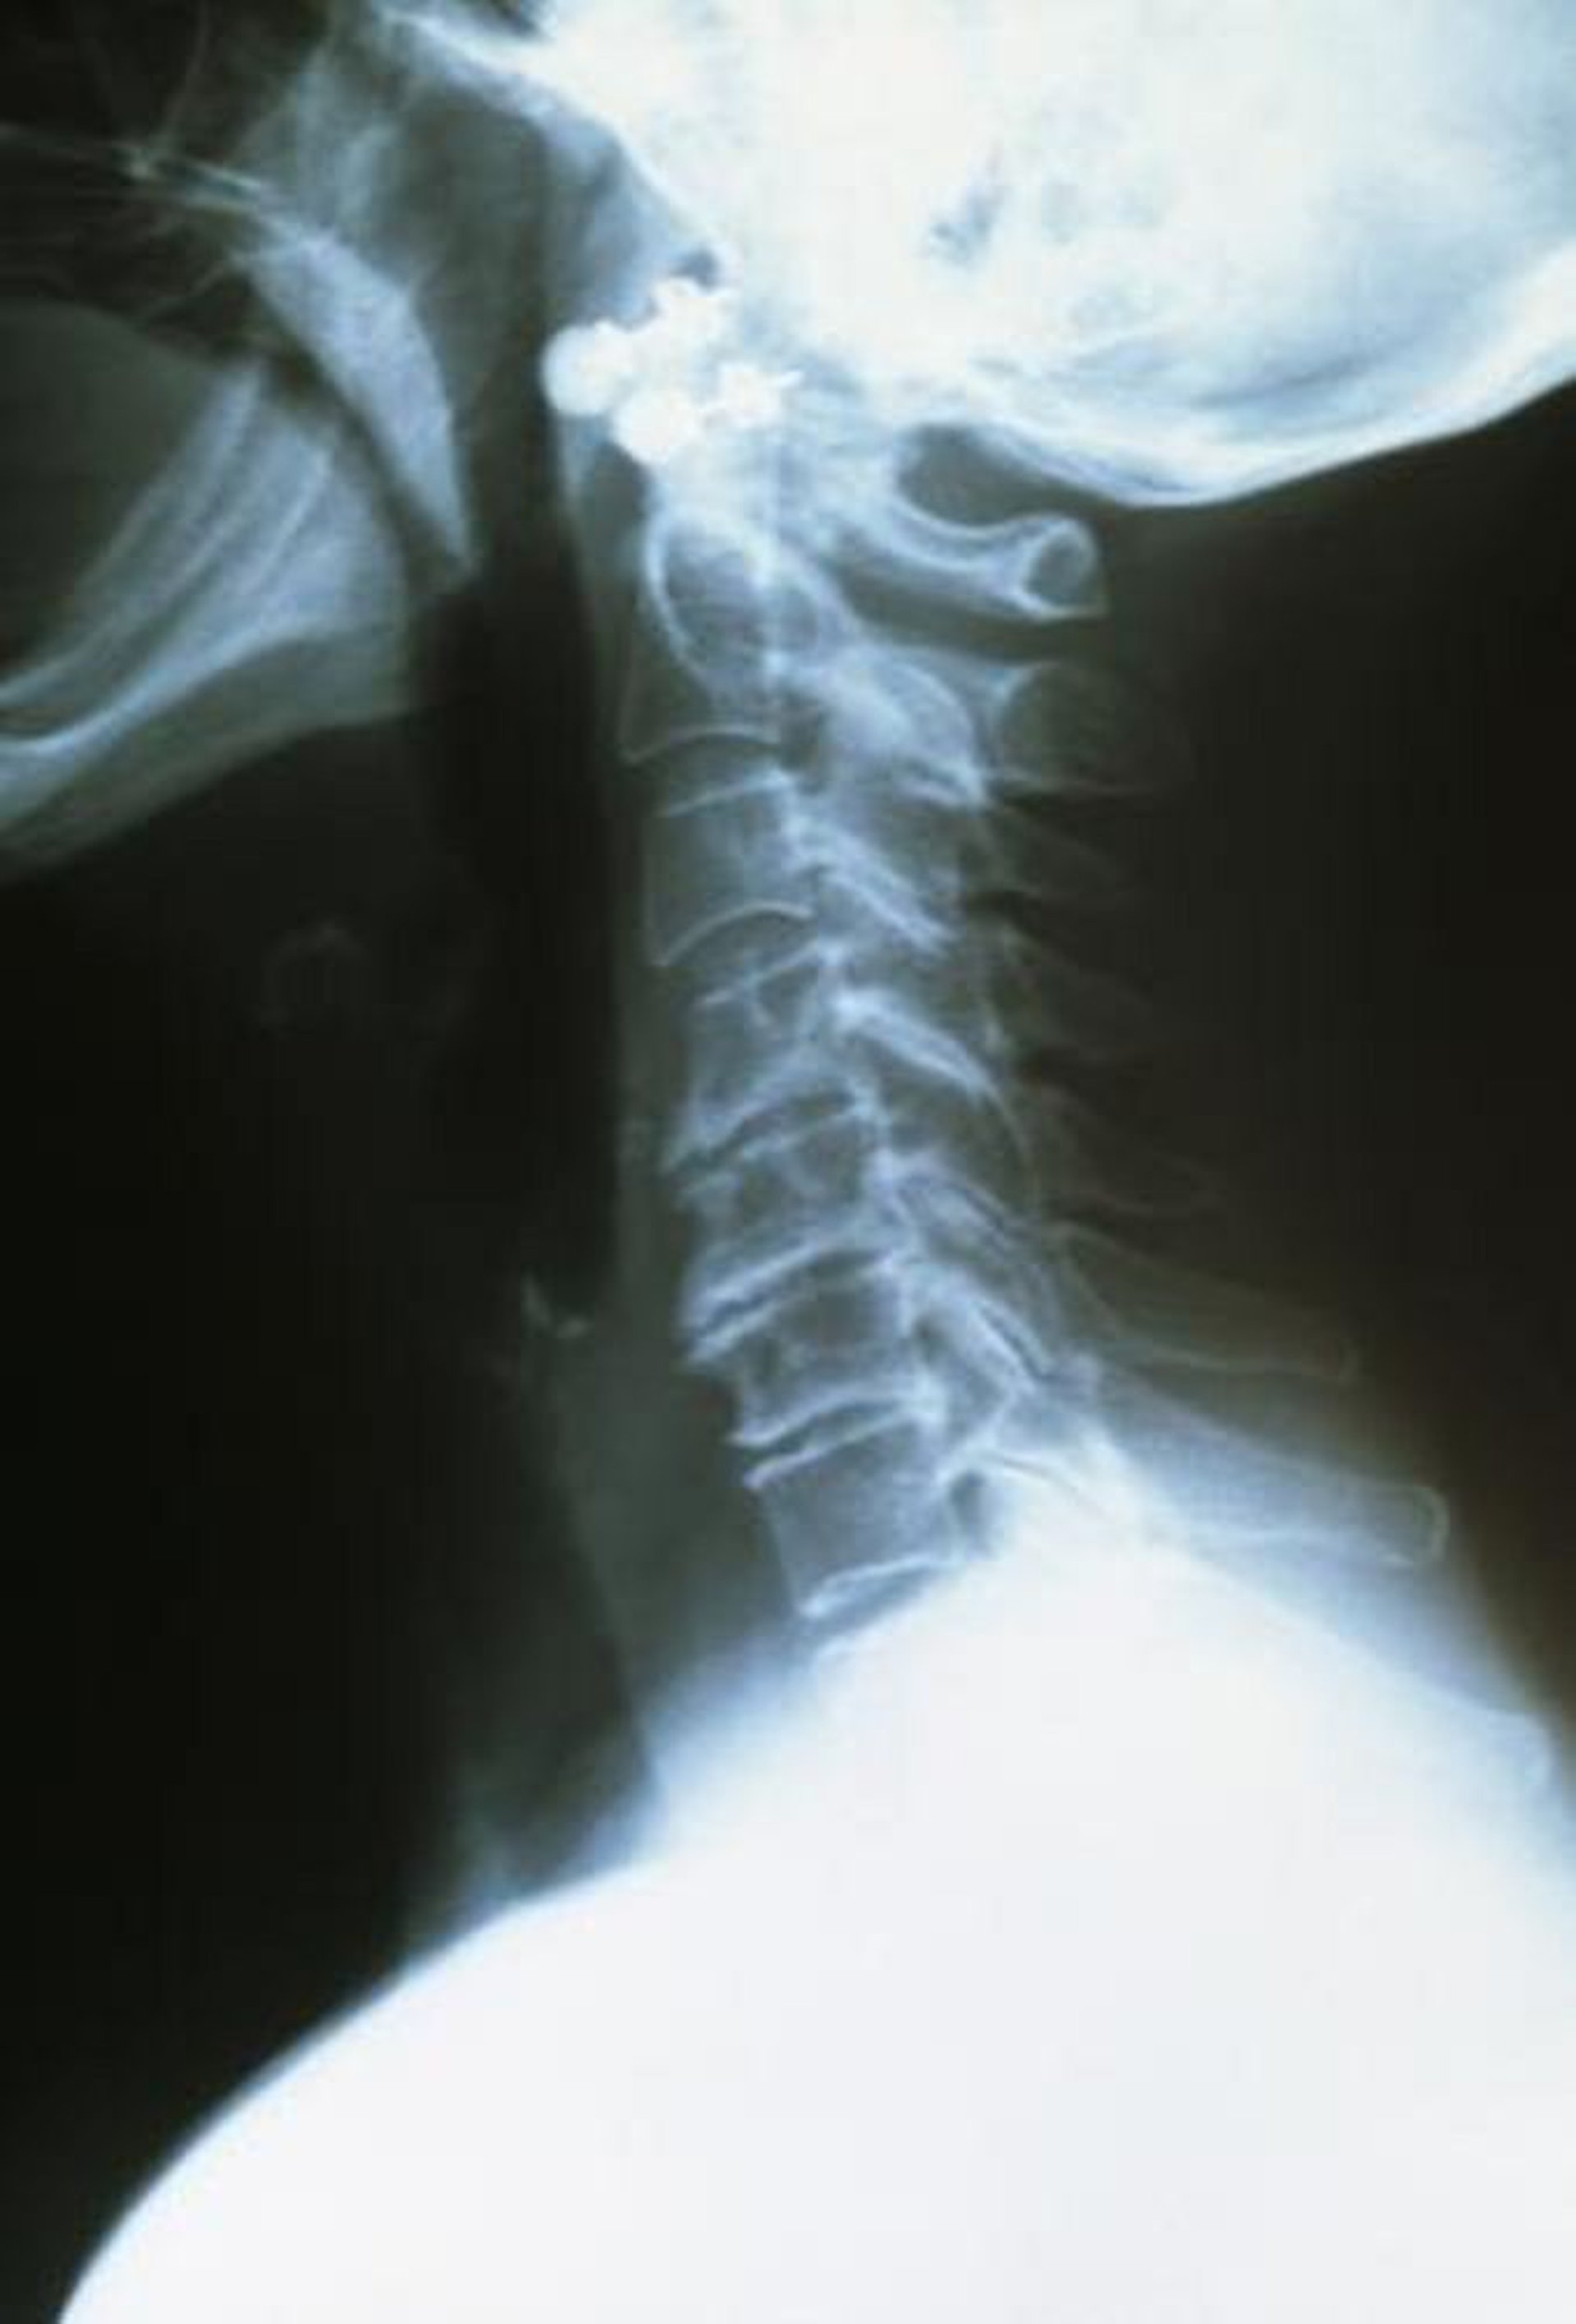

Arthrose cervicale

Les vertèbres cervicales supérieures sont saines, bien espacées et à bords lisses. Les vertèbres inférieures arthritiques sont plus rapprochées et ont des bords rugueux et irréguliers.

DR P. MARAZZI/SCIENCE PHOTO LIBRARY